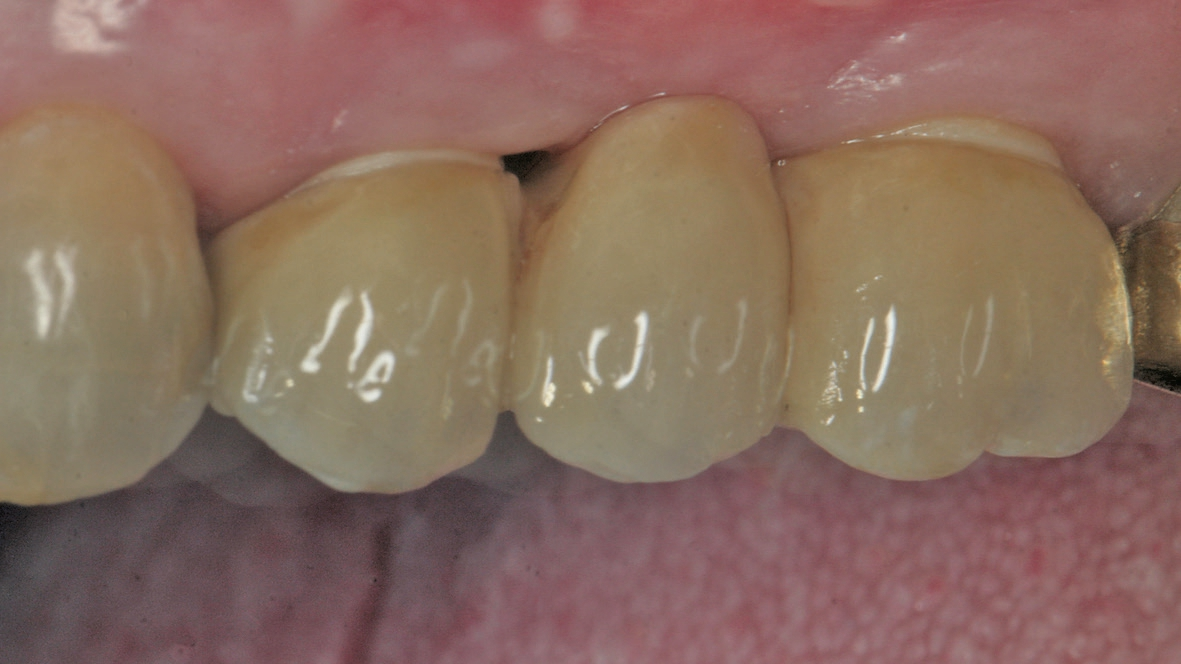

Eine der häufigsten Indikationen für Implantate überhaupt stellt die Einzelzahnlücke nach Verlust eines ersten Molaren dar. Bei den meisten Fällen liegt ein stabiles vertikales Knochenangebot an den Nachbarzähne vor, sodass in der Regel nach Ausheilung des apikalen Granulationsgewebes von einer guten Knochenregeneration auszugehen ist, so dass keine Notwendigkeit der Insertion von kurzen oder ultrakurzen Implantaten gegeben ist. Im Oberkiefer kann bei einer weiten Divergenz der Wurzeln des extrahierten Zahnes es zu einer ausgeprägten Pneumatisation der Kieferhöhle kommen. Daher werden gerade beim jugendlichen Patienten dort dann kurze Implantate eingesetzt, um auf eine Sinusbodenelevation mit einem lateralen Zugang verzichten zu können [3]. Die Implantate können mit oder ohne eine Navigationsschablone gesetzt werden [4]. Da die Lücke begrenzende Nachbarzähne eine gute Orientierung in der mesio-distalen Dimension ermöglichen, kann oftmals auch auf eine Orientierungsschablone verzichtet werden. In der oro-vestibulären Richtung muss der Anwendung des größeren Durchmessers Rechnung getragen werden. Dies kann mit einfachen Positionierungshilfen erfolgen, damit die Implantatachse möglichst zentral in der Kaufläche zu liegen kommt (Abb. 1-8). Die Einzelzahnlücke kann mit einer integrierten verschraubbaren Abutment-Hybrid-Krone oder mit einem Abutment und einer zementierten Krone versorgt werden [5].

Bei der Verwendung einer Klebebasis kann ein mit der Anschlussgeometrie versehener CAD/CAM-Block verwendet werden [9]. Diese stehen als Grünling aus Zirkonoxid- oder Lithium-Disilikat- Glaskeramik (LS2) zur Verfügung, um den Zahnersatz zu fräsen [10]. Nach dem Sintern und dem Einfärben der Zirkonoxidkeramik (ZrO) steht ein korrosionsresistentes, aber in der Regel auch sehr hartes Werkstück zur Verfügung. Daher finden vermehrt LS2-Keramiken Verwendung, die zwar im Vergleich zur Zirkonoxidkeramik eine geringe Biegefestigkeit zeigen, aber für die Anwendung auch für den Seitenzahnbereich freigegeben sind. Klinisch zeigt sich eine geringe Komplikationsrate und vor allem eine hohe Patientenakzeptanz [11]. Neben dem physiologischen Kauverhalten durch die geringere Härte zeichnet sich die LS2-Keramik durch eine bessere Transparenz im Vergleich zu den ZrO-Keramiken aus, so dass besonders im sichtbaren Bereich ästhetisch ansprechende Versorgungen erreicht werden können.